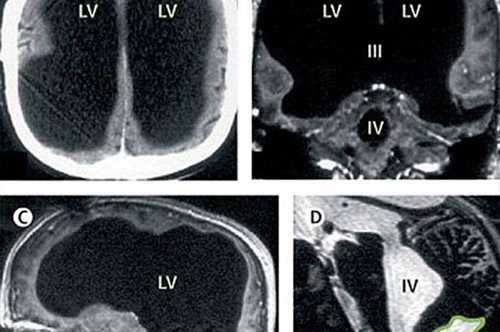

男子大腦消失過半:X光片顯示,75%的腦組織已消失

著名醫學雜志《柳葉刀》披露,2007年,法國一名男子曾因腿部疼痛去醫院檢查,醫生卻找不出病根。在對其進行了全身體檢后才發現,原來這名男子的腿疼是由腦部病變引起的,而該男子的大腦只剩下正常人大腦體積的一半都不到了,他左右半腦上的額葉、頂葉、顳葉及枕葉都萎縮了。

在對這名男子的病史進行詳細調查后發現,原來他童年時患有后天腦積水癥。但在他14歲時,經歷了分流術,隨后的30年,這名男子和家人都以為完全康復了。但其實他的大腦還是在病變,最終,腦內的積水損壞了腦組織,導致其大腦50%至75%的部分都消失了。